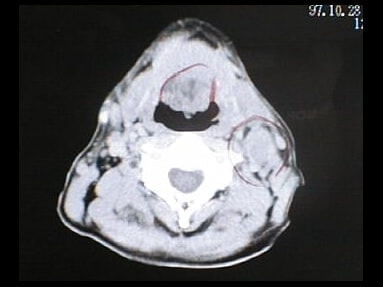

CT画像比較

中咽頭末期がんCT画像①

入院当時CT画像①

中咽頭末期がん消滅CT画像①

入院3か月後癌消滅CT画像①